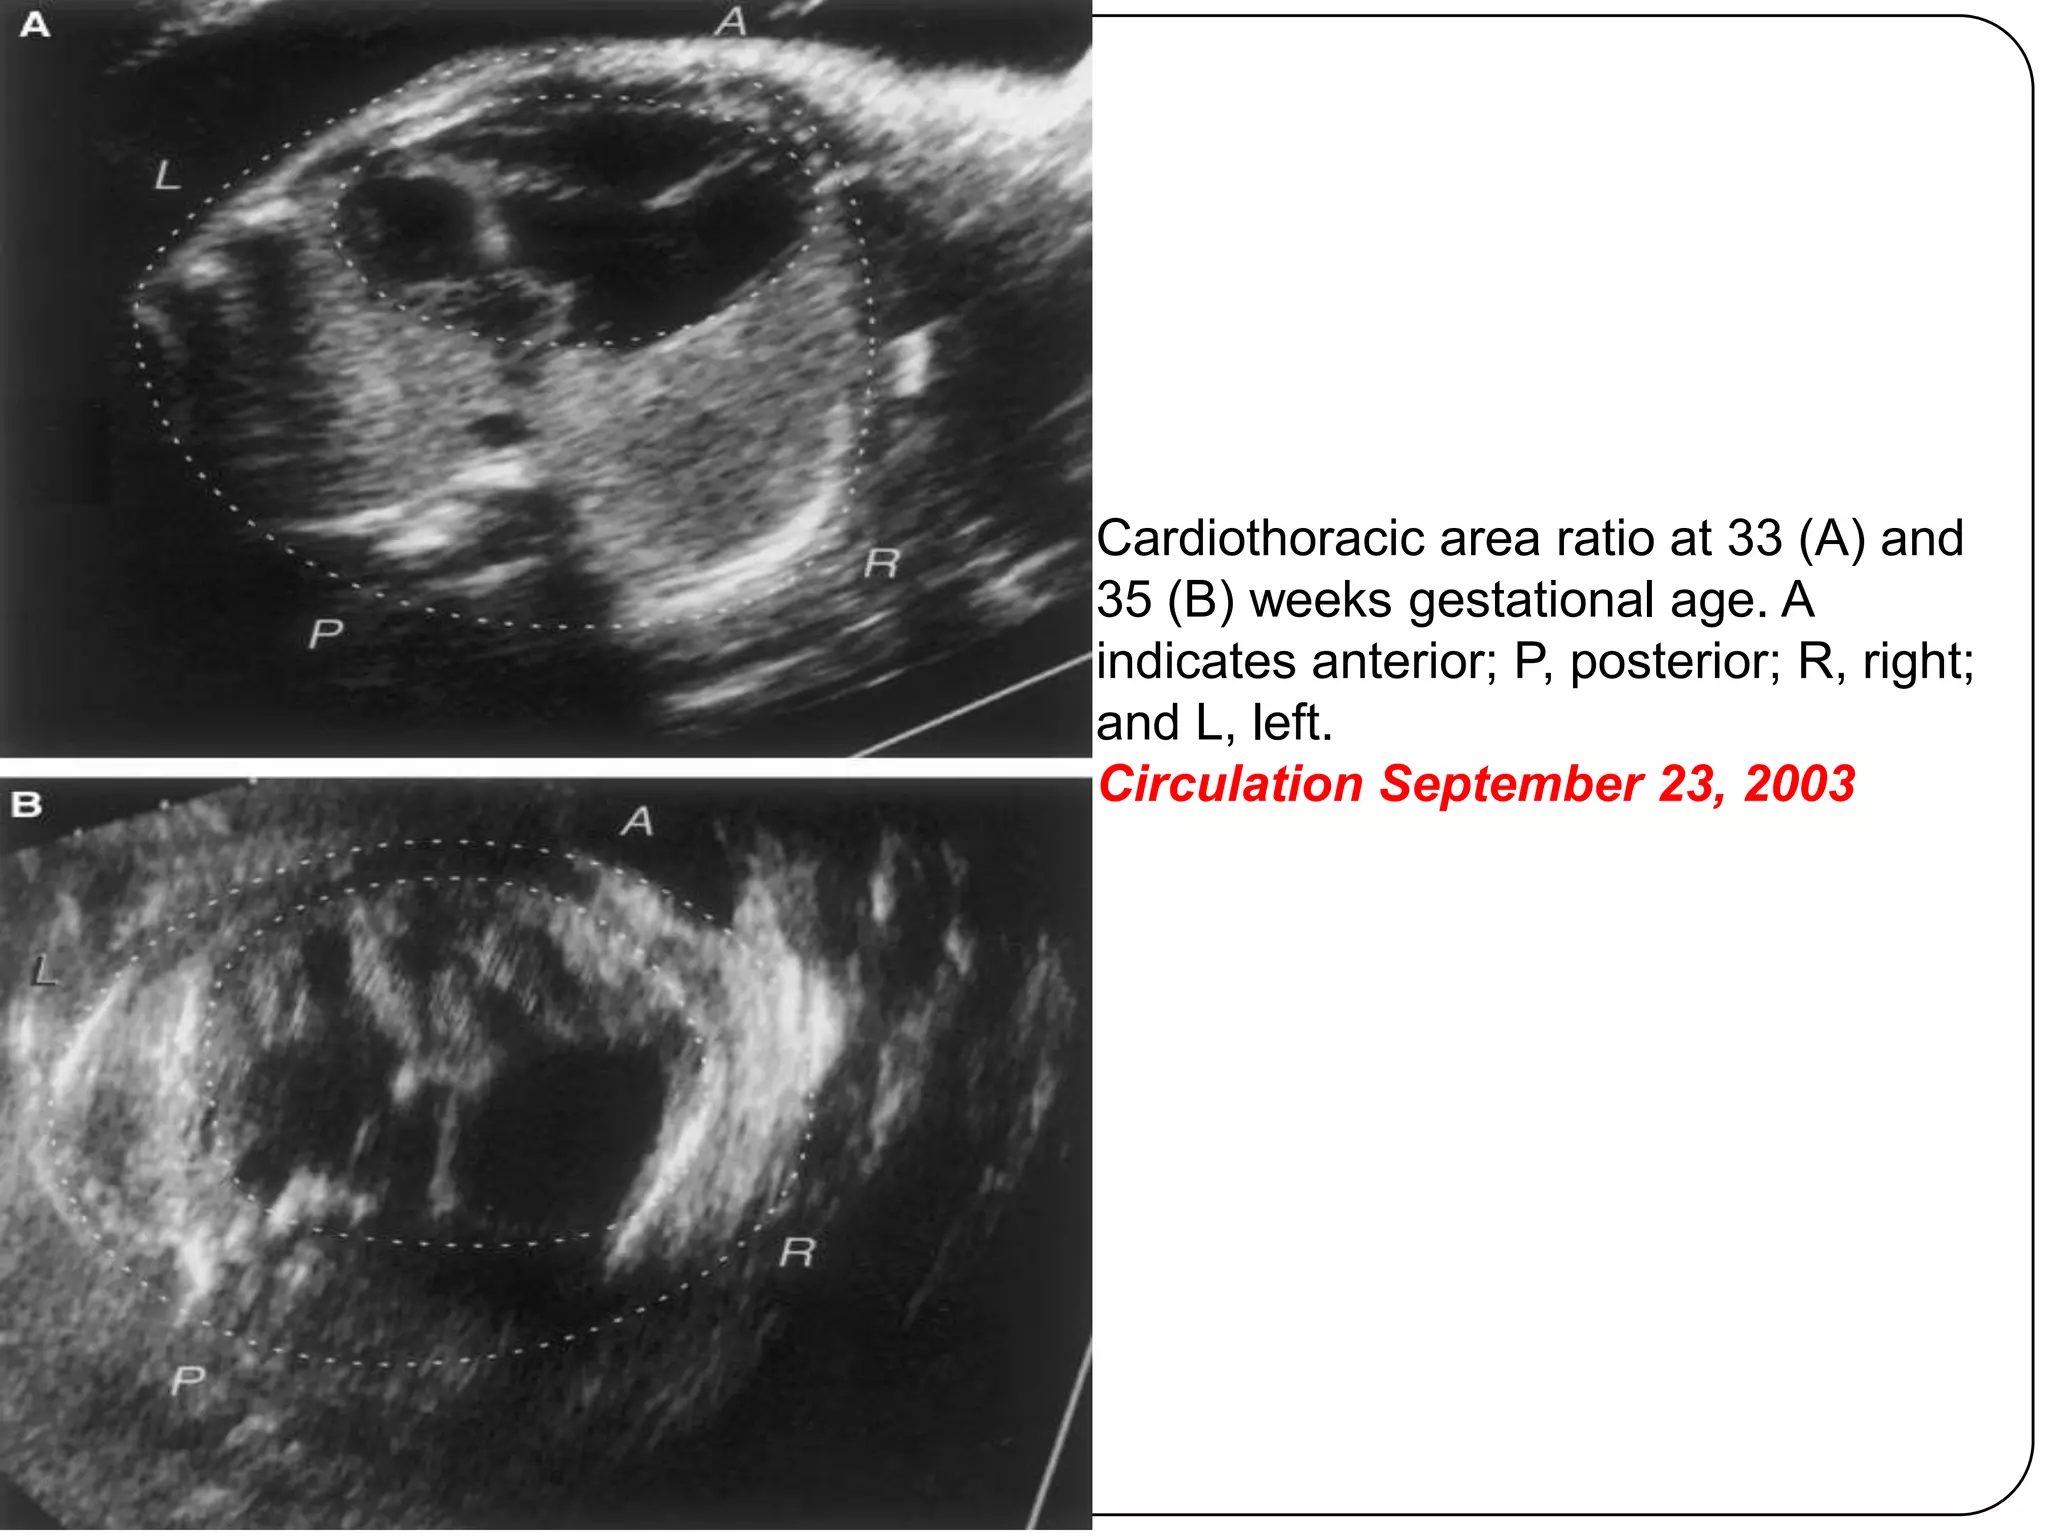

Prenatal presentation

 Difficult to diagnose prenatally

 Fetal presentation is variable: possible

features include cardiomegaly, RA

enlargement, tricuspid regurgitation or

dysplasia, arrhythmia, or fetal hydrops

 Prognosis for the fetus diagnosed in utero

with significant tricuspid valve disease is very

poor (20% survival)

 Progressive right heart dilatation

 Cardiac failure

 Lung hypoplasia

 Pulmonary stenosis/atresia

Cardiothoracic area ratio at 33 (A) and

35 (B) weeks gestational age. A

indicates anterior; P, posterior; R, right;

and L, left.

Circulation September 23, 2003